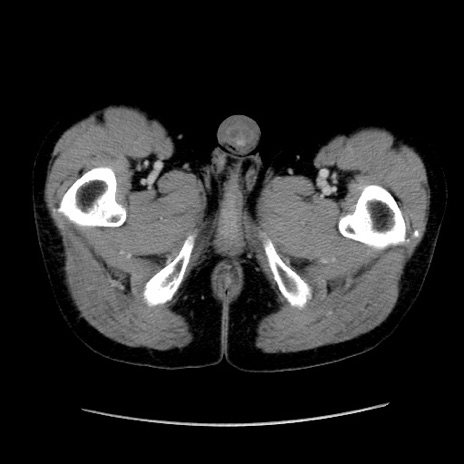

症例37(横断像)

【症例】40歳代 男性

【主訴】腹痛

【現病歴】4時間ほど前に電車に乗車中に臍部上より腹痛出現。徐々に増悪し起立困難となり、救急外来受診。生ものは数日食べていない。今朝お雑煮を食べた。

【身体所見】BT 36.8℃、BP 117/84mmHg、HR 91/min、SpO2 97%、苦悶様、腹部:臍上部広範囲圧痛あり、反跳痛±

【データ】WBC 8100、CRP 0.03